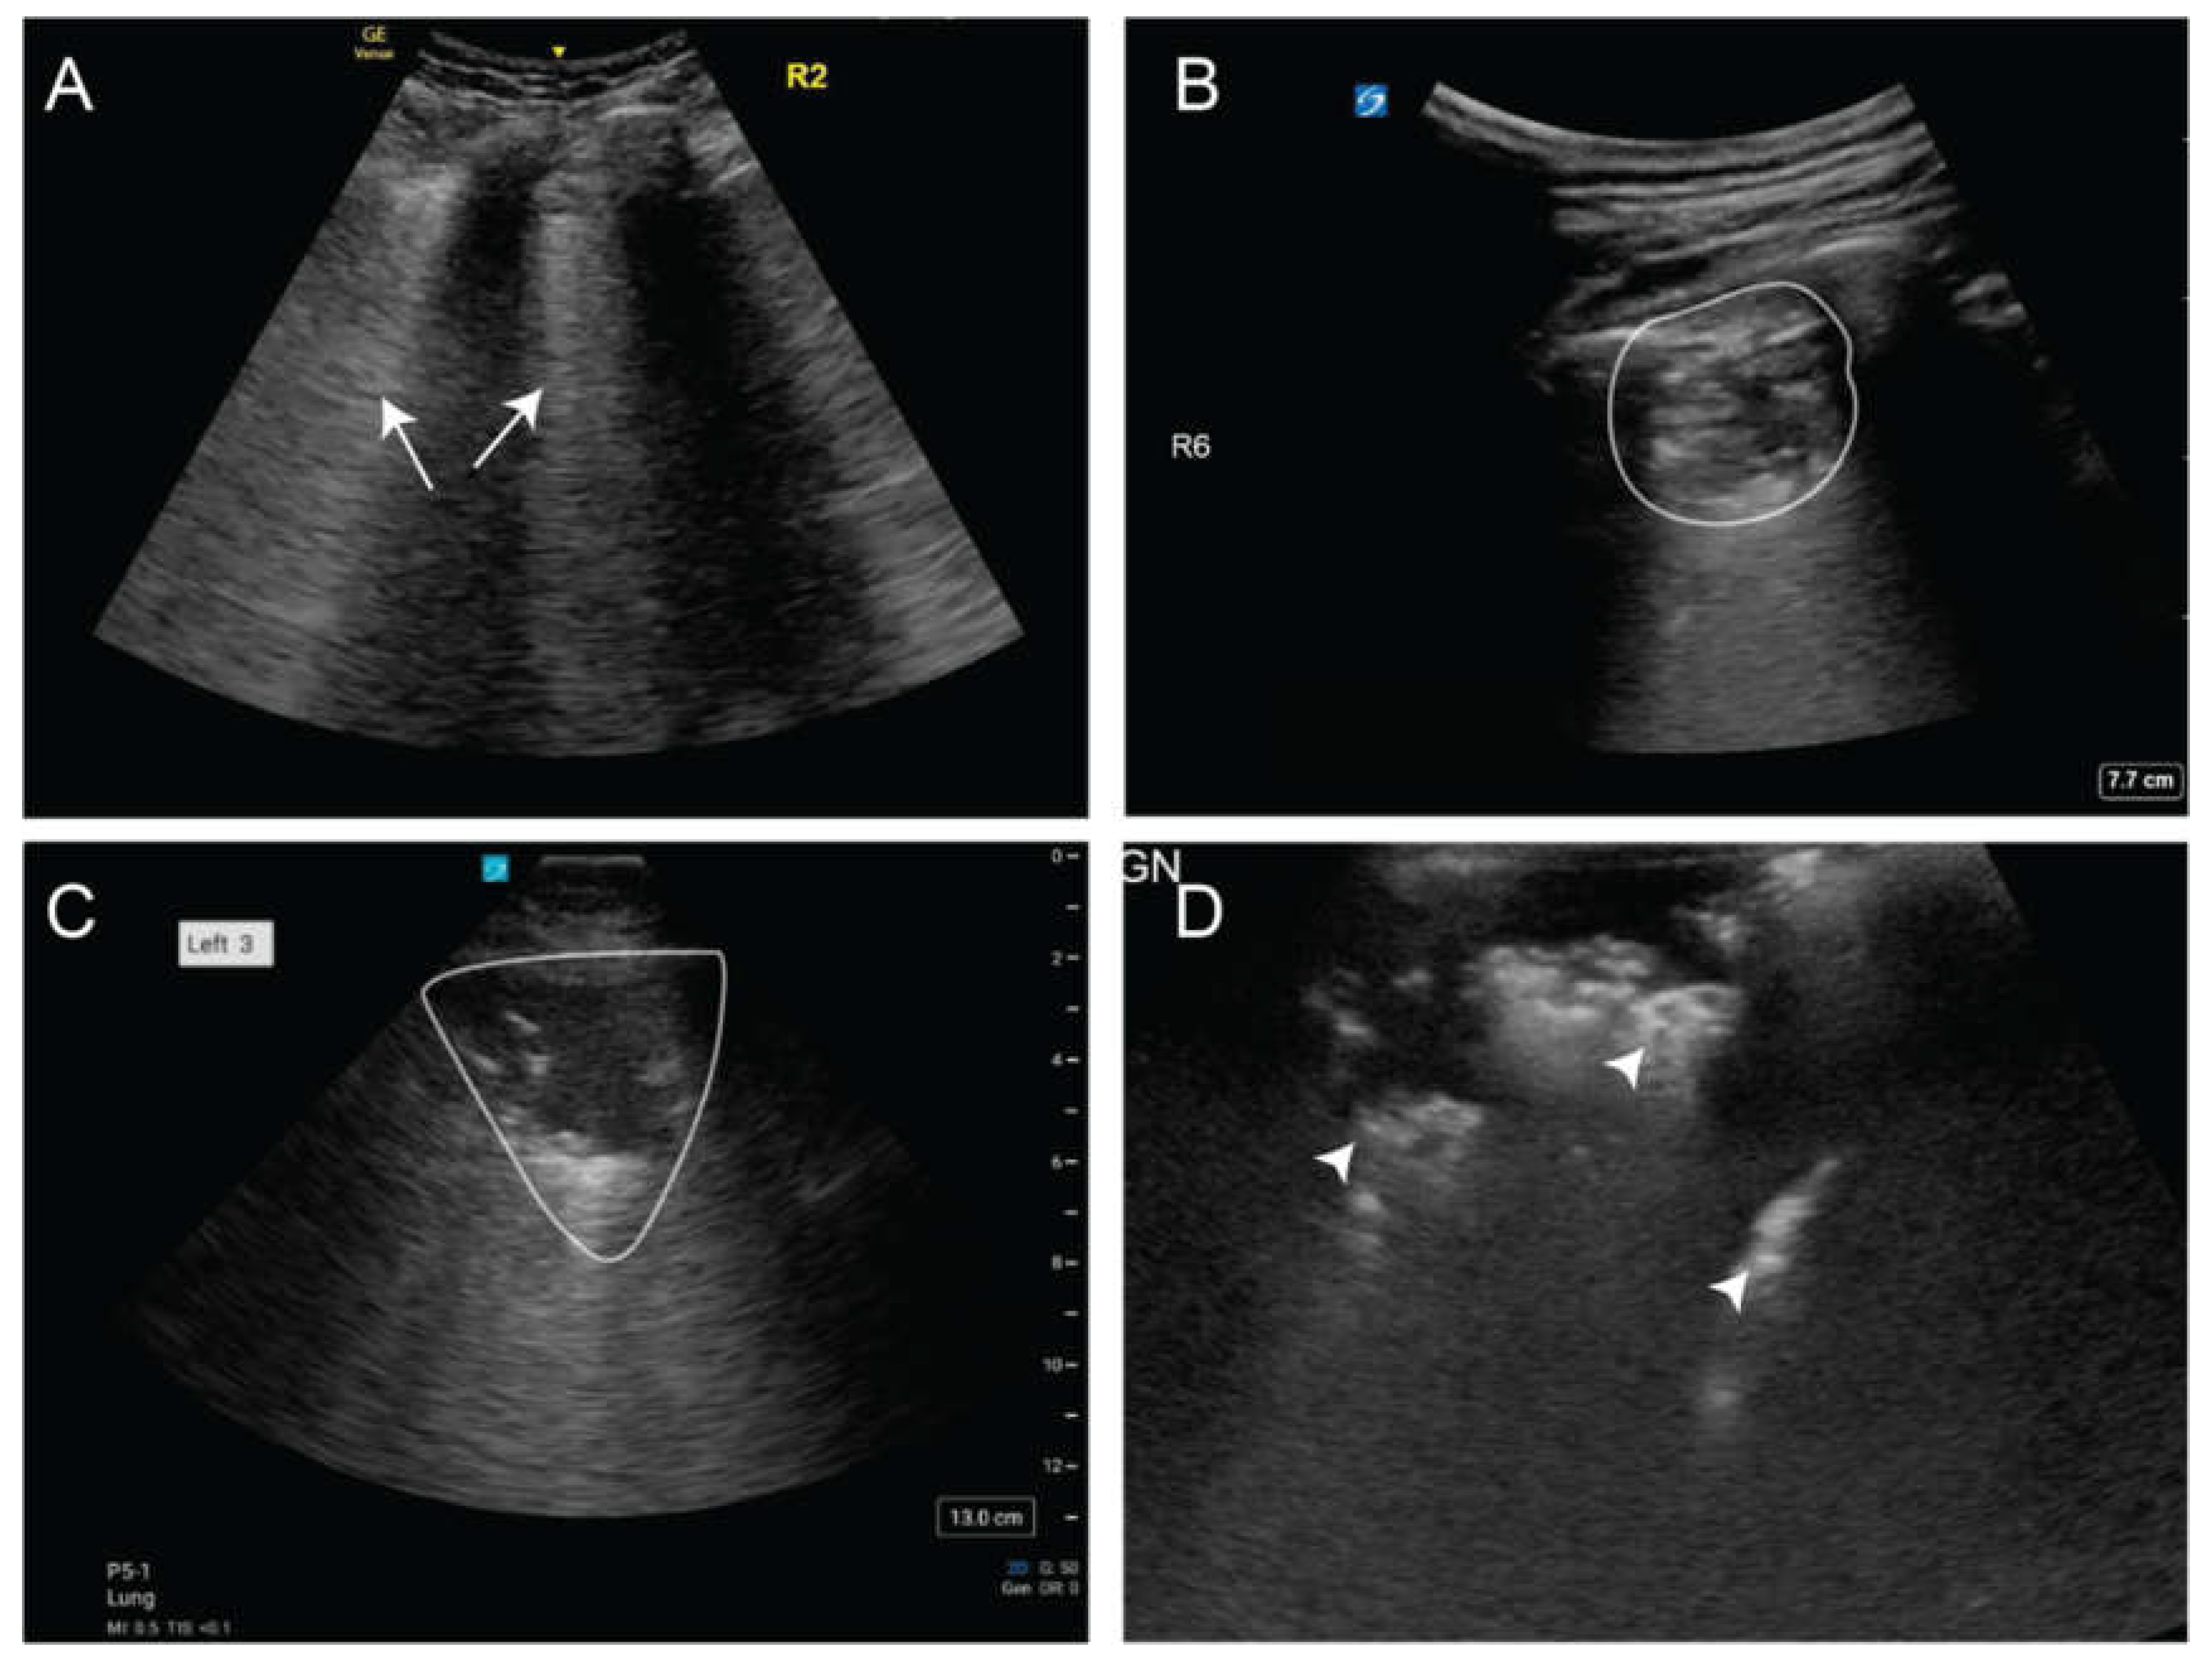

6.3. Pneumonia and Empyema

Pneumonia is a leading cause of hospitalization, with approximately 6 million cases reported annually in the United States [52]. Sonographically, pneumonia typically presents as focal B-lines, subpleural consolidations, and dynamic air bronchograms which are echogenic branching structures that move with respiration, indicating patent airways within consolidated lung (Figure 11). LUS has shown high diagnostic accuracy for community-acquired pneumonia, with a sensitivity of 93.4% and specificity of 97.7%, comparable to CT scan-based diagnosis [53,54]. It outperformed CXR in detecting lung consolidation (93.8% vs. 75%) and patchy shadowing (94.1% vs. 52.9%) and identified pleural thickening in 95.2% of cases by day 6, whereas CXR detected none (p < 0.001) [5,55]. Additionally, the presence of dynamic air bronchograms on LUS is particularly useful in differentiating pneumonia from resorptive atelectasis, with a specificity of 94% and a positive predictive value of 97% [53]. LUS has also proven effective in assessing post-infectious lung injury, reinforcing its role as a reliable bedside diagnostic tool.

Figure 11. A) Isolated areas of B-lines (arrows) consistent with pneumonia B) Subpleural consolidation (white outline) C) Large consolidative pneumonia (white outline) D) Air bronchograms (white arrowheads).